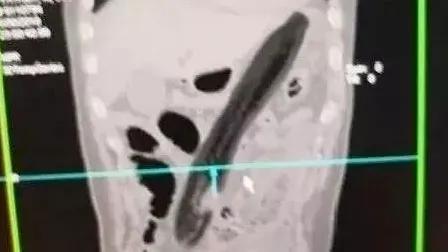

西南医科大学附属中医医院肛肠科主任李五生教授说:直肠异物是直肠里出现除了粪便以外的其他东西,比如灯泡、按摩棒、玻璃药瓶、陀螺、蜡烛、圆柱形金属瓶等等,甚至常见的蔬菜和长条状的物体,比如黄瓜、火腿肠、茄子、苦瓜、黄鳝、泥鳅……

以上结构使得经口吞入的长条型物体容易嵌顿于转弯处,针刺样物体容易阻留于直肠窦处,而经肛门进入的物体容易吸到直肠壶腹部。